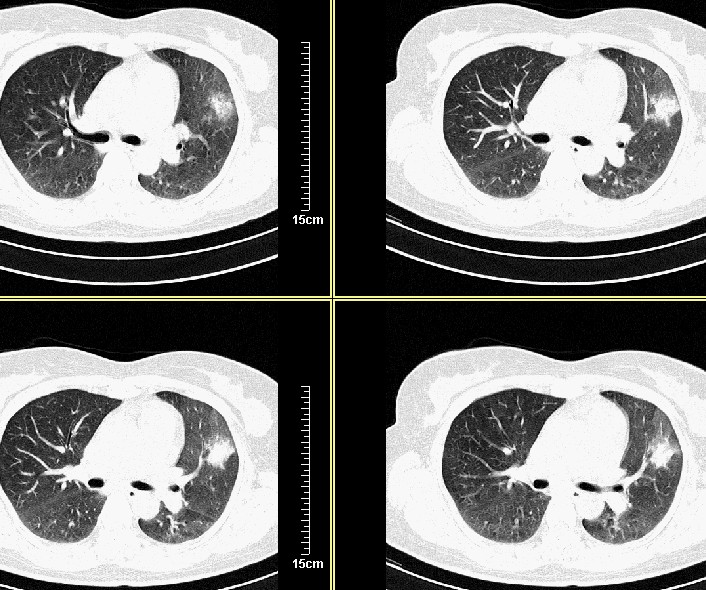

病变在三天之内消散,只能考虑是:过敏性肺炎。

3天后复查:病变明显好转、吸收:考虑炎症可能性大

才三天的时间,病灶明显吸收,还是支持炎症,可继续治疗复查。

病灶似乎呈片样,密度不均匀,3天后复查:病变明显好转、吸收:考虑炎症可能性大 。

气管注药后3天后复查:病变明显好转、吸收:考虑炎症可能性大,肺癌待排!